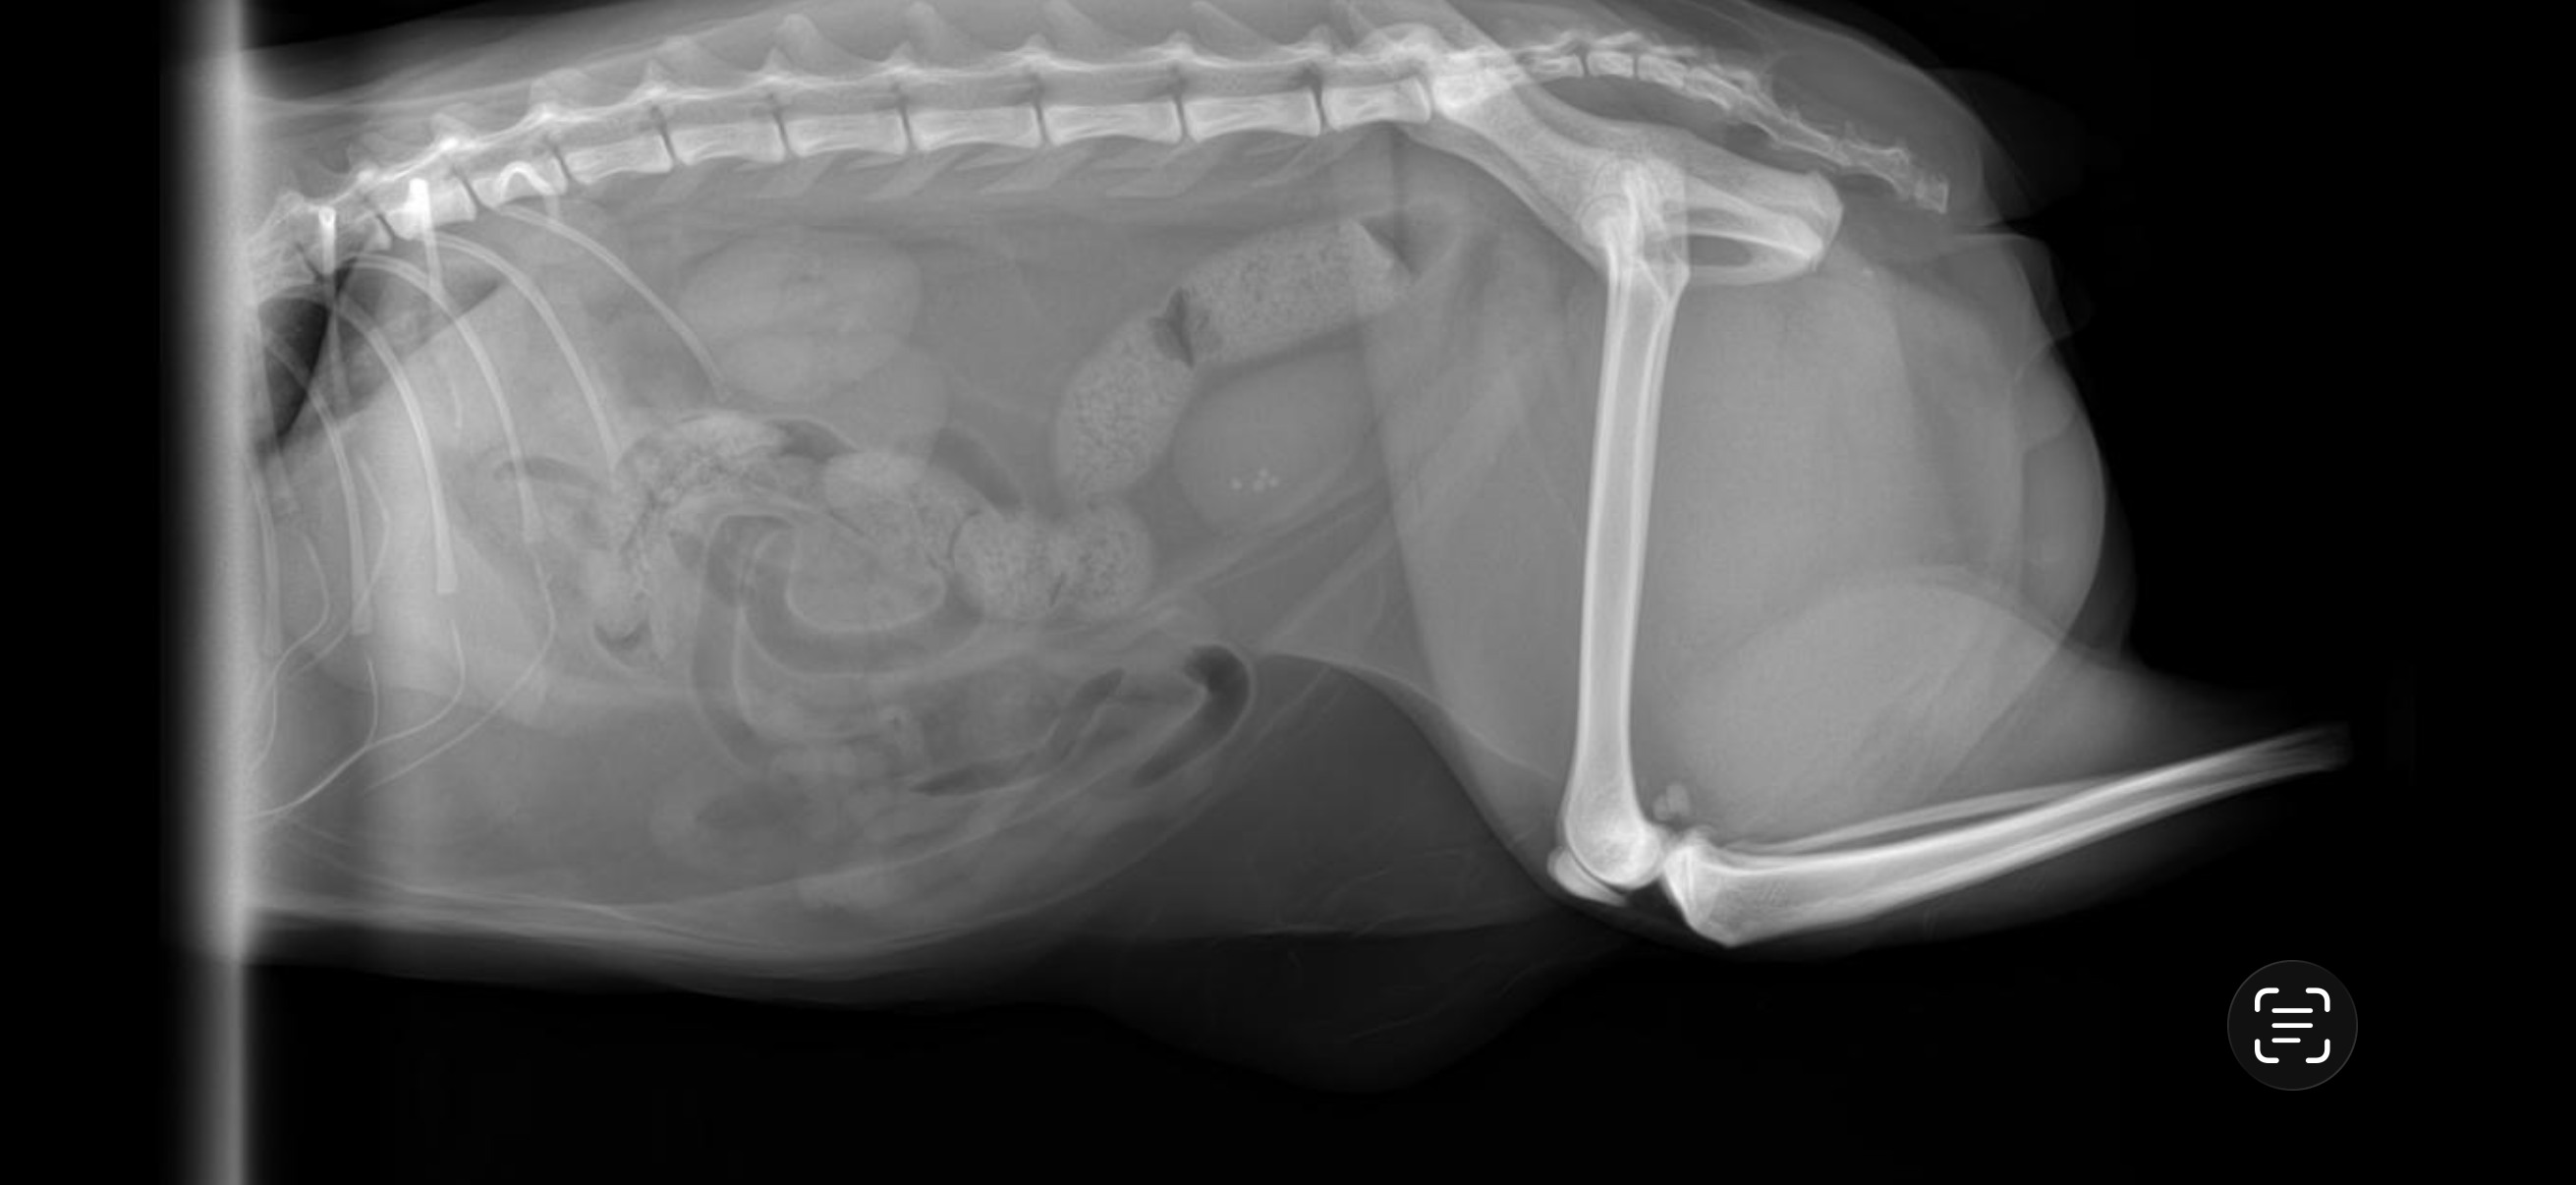

Description: Buddy is my four-year-old bobtail cat and my constant companion. Recently, he was diagnosed with bladder stones. We've been treating him with antibiotics and prescription urinary tract food, but on his last visit, an X-ray showed that one of his stones had traveled into his urethra. While he isn't blocked at this time, he urgently needs a cystotomy surgery to prevent a life-threatening emergency.